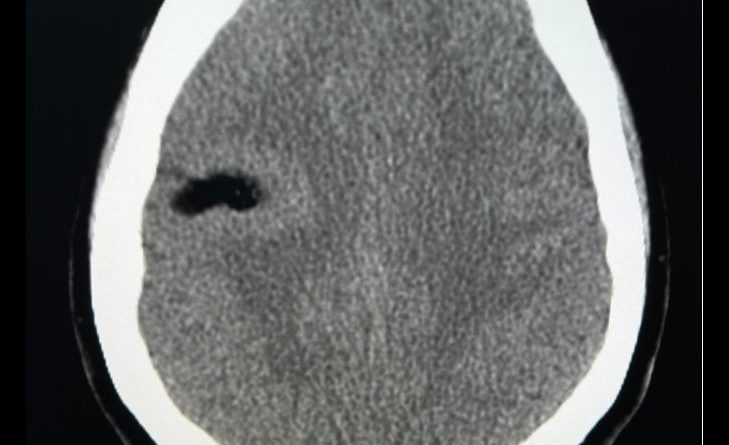

- A) Aksiyel kontrastsız BT’de lezyon yağ dansitesinde (-81HU) (kalın ok) izlenmekte olup lezyon etrafındaki korteks kalın görünümdedir (ince ok).

- BT’de düşük dansiteli kontrastlanmayan lezyon (−40 ila −100 HU)